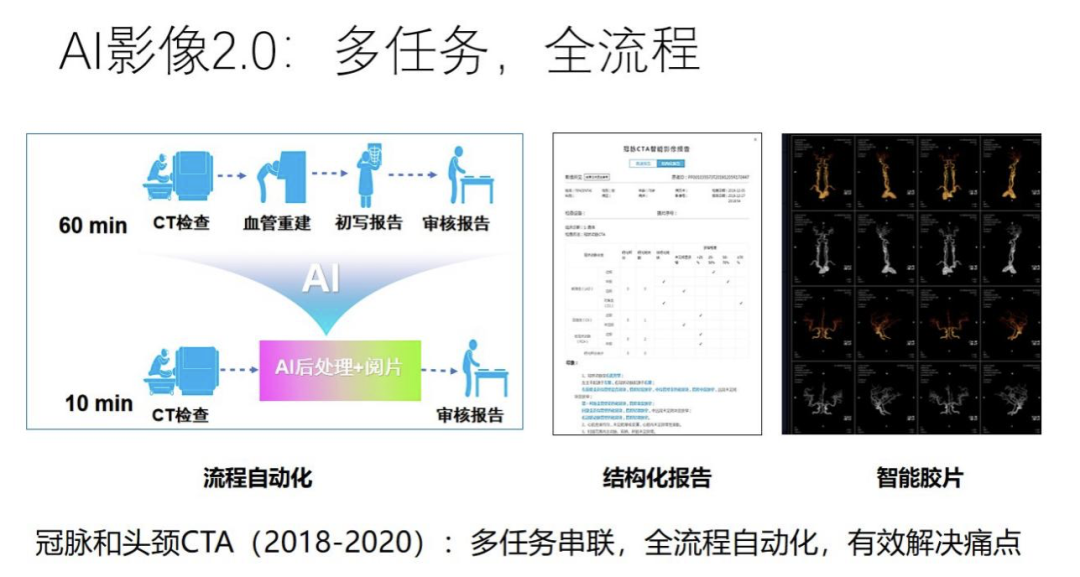

到了 2018、2019 年,AI 影像的产品开始从单任务、单环节拓展到多任务、全流程的场景,我们称之为 2.0 阶段。其中一个比较有代表性的产品就是数坤科技做的冠脉和头颈 CTA,涉及到多个算法任务串联起来的流程,只有这个流程全部自动化之后,才可以为医生提供比较大的价值,解决医疗行业的痛点。如图所示,传统流程可能需要花 60 分钟才能完成这些步骤,而在 AI 流程下,很多环节被自动化的算法取代,因此只需花费 10 分钟,效率大大提高,这就是 2.0 产品带给医疗场景的价值。